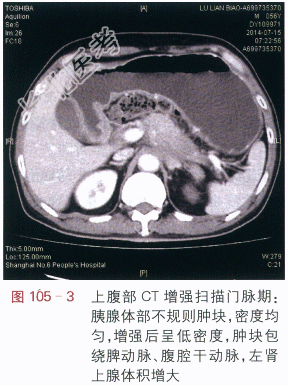

读片分析:上腹部CT平扫显示胰腺体部增大,密度均匀,尾部萎缩,胰腺周边模糊(见图105-1),增强扫描动脉期:胰腺体部不规则肿块,增强后动脉期呈低密度,肿块边缘不清,肿块包绕脾动脉、腹腔干动脉(见图105-2);门脉期:胰腺体部不规则低密度肿块,肿块包绕脾静脉(见图105-3)。延时期肿块密度呈低密度,肿块包绕腹腔血管、并向周边侵犯,左肾上腺体积增大(见图105-4)。